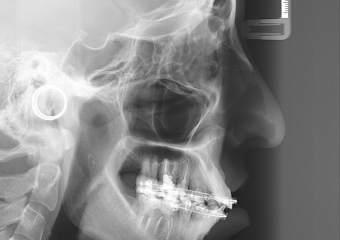

Telerradiografia inicial

Telerradiografia após a cirurgia